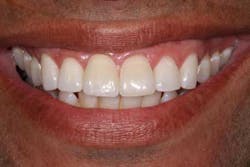

Usain Bolt trained for years to prepare for a 10-second Olympic race, a race that made him a world superstar. He didn’t walk up to the track the day of the Olympics and blow away the competition. He spent countless hours preparing physically and mentally for that one moment in the spotlight. The same dedication applies to dentistry. When an anterior implant case is planned properly among the surgeon, dentist, and ceramist, the result can be as rewarding as Olympic gold.Before

Before